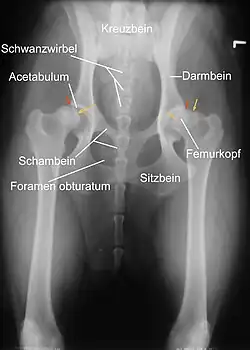

Eine zuverlässige Möglichkeit, den Schweregrad der Erkrankung zu erkennen, ist die Röntgenuntersuchung. Dabei müssen die Gelenke überstreckt werden, was beim Vorliegen einer HD starke Schmerzen verursacht. Daher wird sie unter Kurznarkose durchgeführt. Voraussetzung für eine aussagekräftige Diagnose ist die exakte Positionierung des Tieres in Rückenlage mit gestreckten, parallel gelagerten Oberschenkeln und rechtwinklig zum Strahlengang eingedrehten Kniescheiben. Die ordnungsgemäße Lagerung kann anhand der Form der Foramina obturatoria, der Form der Darmbeinschaufeln, der Breite der Darmbeinsäulen und der Position der Kniescheiben beurteilt werden. Zusätzliche Aufnahmen können in „Froschhaltung“ der Oberschenkel oder im seitlichen (latero-lateralen) Strahlengang erfolgen, in Deutschland wird dies nur bei Obergutachten durchgeführt.[3]

Man unterscheidet bei der Beurteilung primäre Kriterien wie die Ausformung des Hüftgelenks und Feststellung einer Inkongruenz, der Grad der Lockerheit des Gelenks und die Ausformung der Gelenkpfanne und des Hüfkopfes sowie sekundäre Kriterien, welche auf eine Arthrose hinweisen.[3]

Die Beckenpfanne sollte tief ausgebildet sein und mit dem Kopf des Oberschenkelknochens einen gleichmäßigen, schmalen und parallel verlaufenden Gelenkspalt bilden. Die vordere Kontur des Acetabulums sollte rund auslaufen. Die Verdichtung (Sklerose) am vorderen Pfannenrand sollte gleichmäßig und fein gezeichnet sein. Ist sie zum seitlichen Pfannenrand hin betont und nach innen vermindert spricht dies für eine stärkere Belastung des äußeren Gelenkbereiches und damit für eine erhöhte Instabilität. Der gesunde Hüftkopf ist kugelförmig, ohne Auflagerungen und sein Zentrum liegt innenseitig des oberen Pfannenrandes.[3]

Ein wesentliches Auswertungskriterium ist der Norberg-Winkel. Er ist als der Winkel definiert, der zwischen der Verbindungslinie der Zentren der beiden Oberschenkelköpfe und dem jeweiligen vorderen Pfannenrand abgetragen wird (siehe Abbildung). Bei einem HD-freien Tier sollte er mehr als 105° betragen (gelbe Linien).[3]